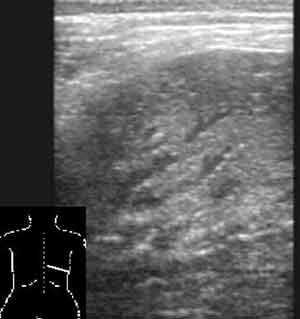

Эхография в диагностике заболеваний легких у детей.

Рис. 3. Пневмонический очаг с заполненными жидкостью бронхами.

Новости лучевой диагностики 2002 1-2: 56-60